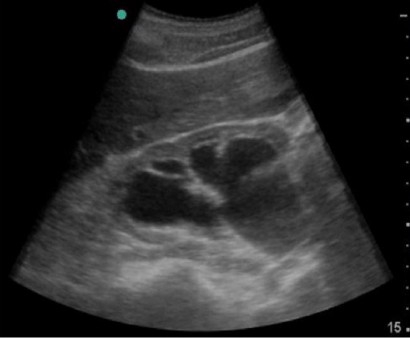

No dilatation calyceal walls are apposed to each other. Um den Harnstau zu erkennen sollten Sie nach verschiedenen Symptome Ausschau halten. Sonographie Niere und Harnleiter.

Dies kann akuter Harnstau sein. Gradeinteilung von Harnstau Beurteilung der Nierenparenchymdicke Suche nach Nierensteinen oder Raumforderunge.

Harnstau Sonographieatlas Erlangen

Harnstau Der Nieren Sonographieatlas